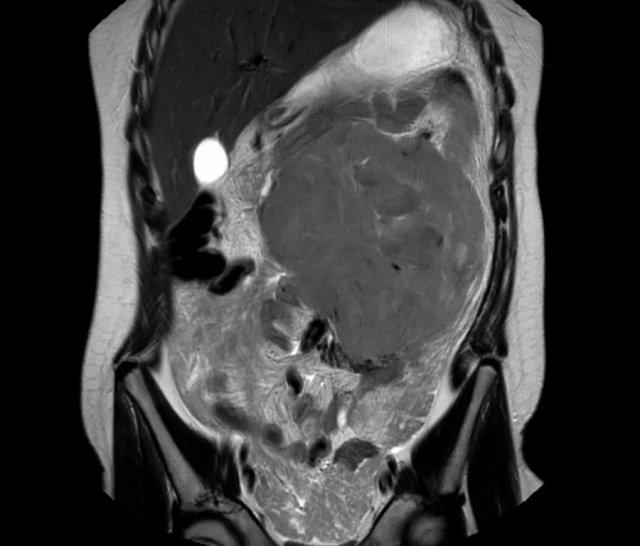

Hình ảnh MRI của một bé gái chín tháng tuổi có khối u ở bụng trái. MRI cho thấy khối u tuyến thượng thận trái, một phần đặc, một phần nang. Có nhiều di căn gan.

Khối u đã được sinh thiết. Có tình trạng chảy máu liên tục qua kim dẫn đường. Vào cuối thủ thuật, hai nút bọt gelatin đã được đặt vào (các dải tăng âm (mũi tên)).

Hình ảnh